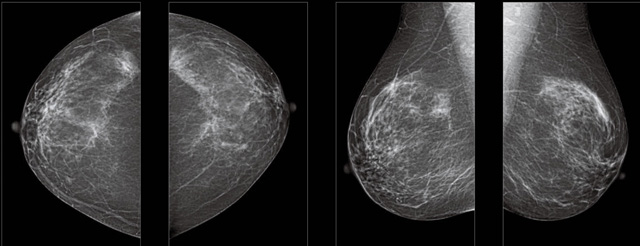

首先不同年齡階段的乳腺篩查頻次種類(lèi)不一樣。青春期女性第二性征明顯發(fā)育開(kāi)始,每個(gè)月進(jìn)行自我乳腺檢查。20-30歲的女性就不推薦進(jìn)行乳腺檢查,因?yàn)槟贻p女性的乳腺組織非常緊急。鉬靶X光線(xiàn)等檢查的射線(xiàn)不能辨別腫塊跟腺體。身體就白吸收了輻射,影響了身體健康。每個(gè)月自檢一次就是在洗澡時(shí)候,對(duì)著鏡子看看乳房外觀(guān)正常,皮膚潰爛、腫塊、顏色改變、再摸一下有沒(méi)小疙瘩。乳腺高危人群,特別是有乳腺CA遺傳傾向的女性,乳腺導(dǎo)管跟小葉不典型增生,原位癌。30歲前有乳房放療的女性。乳腺癌篩查可以把年齡提前到40歲前。40到70歲的女性可以在適合的機(jī)會(huì)篩查。

采用影像檢查技術(shù)來(lái)發(fā)現(xiàn)疑似特定病檢查跟人群的普查。一到兩年進(jìn)行一次X光線(xiàn)的乳腺檢查。記過(guò)是C或者D型,可以加上B超協(xié)同。還可以一年一次核磁共振MRI檢查。70歲以上的女性認(rèn)為絕經(jīng)的女性是比較安全的。實(shí)際上也有乳腺癌的風(fēng)險(xiǎn)。65歲以上風(fēng)險(xiǎn)也很大。也是需要進(jìn)行機(jī)會(huì)性篩查。